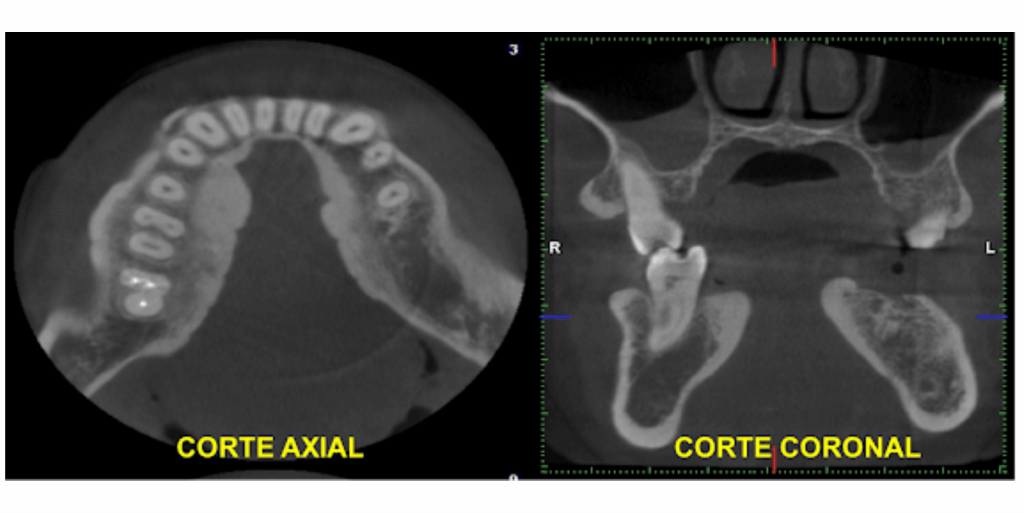

Paciente femenina referida para estudio mediante Tomografía Computarizada de Haz Cónico (TCHC) previa a la  colocación de implantes en la mandíbula. En radiografía panorámica se observó aumento de la densidad del reborde alveolar desde la canina, bilateralmente, a nivel del tercio medio y cervical de las unidades dentarias. En vistas axial y coronal de TCHC, se evidenció engrosamiento óseo dependiente de la tabla ósea lingual, de bordes definidos, con aspecto nodular y lobulado (Figura 1). Las reconstrucciones volumétricas en 3D demuestran la  extensión de dicho engrosamiento (Figura 2). La imagen presentó signos tomográficos de exostosis (Torus mandibular).

Figura 2. Reconstrucciones multiplanares de Tomografía Computarizada de Haz Cónico, evidenciando engrosamiento óseo dependiente de la tabla ósea lingual, de bordes definidos, con aspecto nodular y lobulado, desde la zona canina, en ambos lados de la mandíbula, compatible con Torus Mandibular.